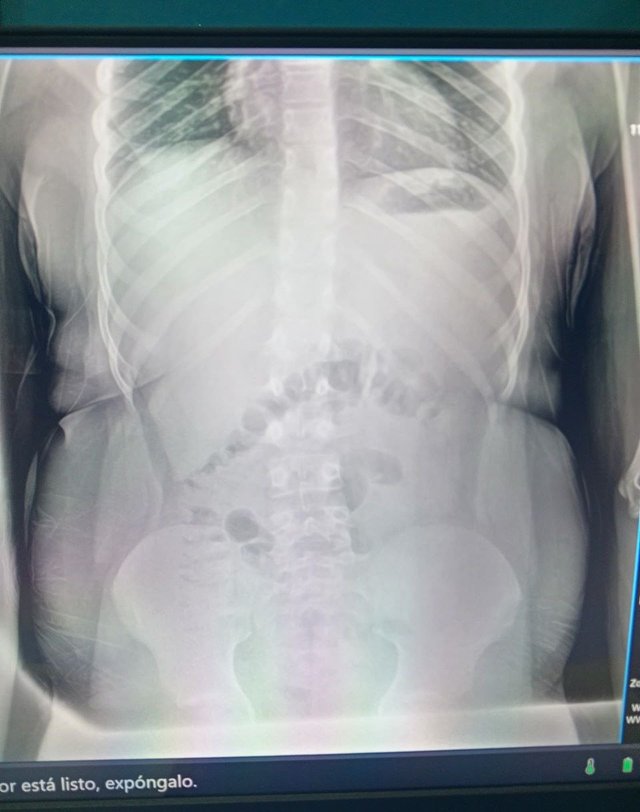

En esta primera semana, vengo con un paciente masculino de 14 años con escoliosis lumbar. Él tiene un historial médico con antecedentes genéticos de escoliosis y dolor durante la infancia que afectaba una pierna sin agnóstico. Acá dejo los rayos X.

El diagnóstico definitivo del paciente fue en 2024, cuando acudió a consulta a los 13 años debido a un dolor lumbar crónico a raíz de un accidente automovilístico, en el cual recibió parte importante del impacto. Fue tratado con tiocolchicósido e ibuprofeno, también requirió del uso de un corsé.

El paciente ha presentado diferentes crisis de dolor crónico que llegan a durar meses. Este dolor también afecta una de sus piernas. Presentó mejoría significativa con los ejercicios lumbares, árnica en gel y bajar de peso.

Task 2 (2.5/2.5)Yes, before reading your post I guessed through X ray that it's scoliosis, that's sad it's genetic scoliosis and even in so early age. But now there are advance treatment option for scoliosis other than physiotherapy. Scoliosis happens like there will be tightness of muscles in one side and weakness in other side. So, the best thing is using orthosis or prothesis with physiotherapy management.